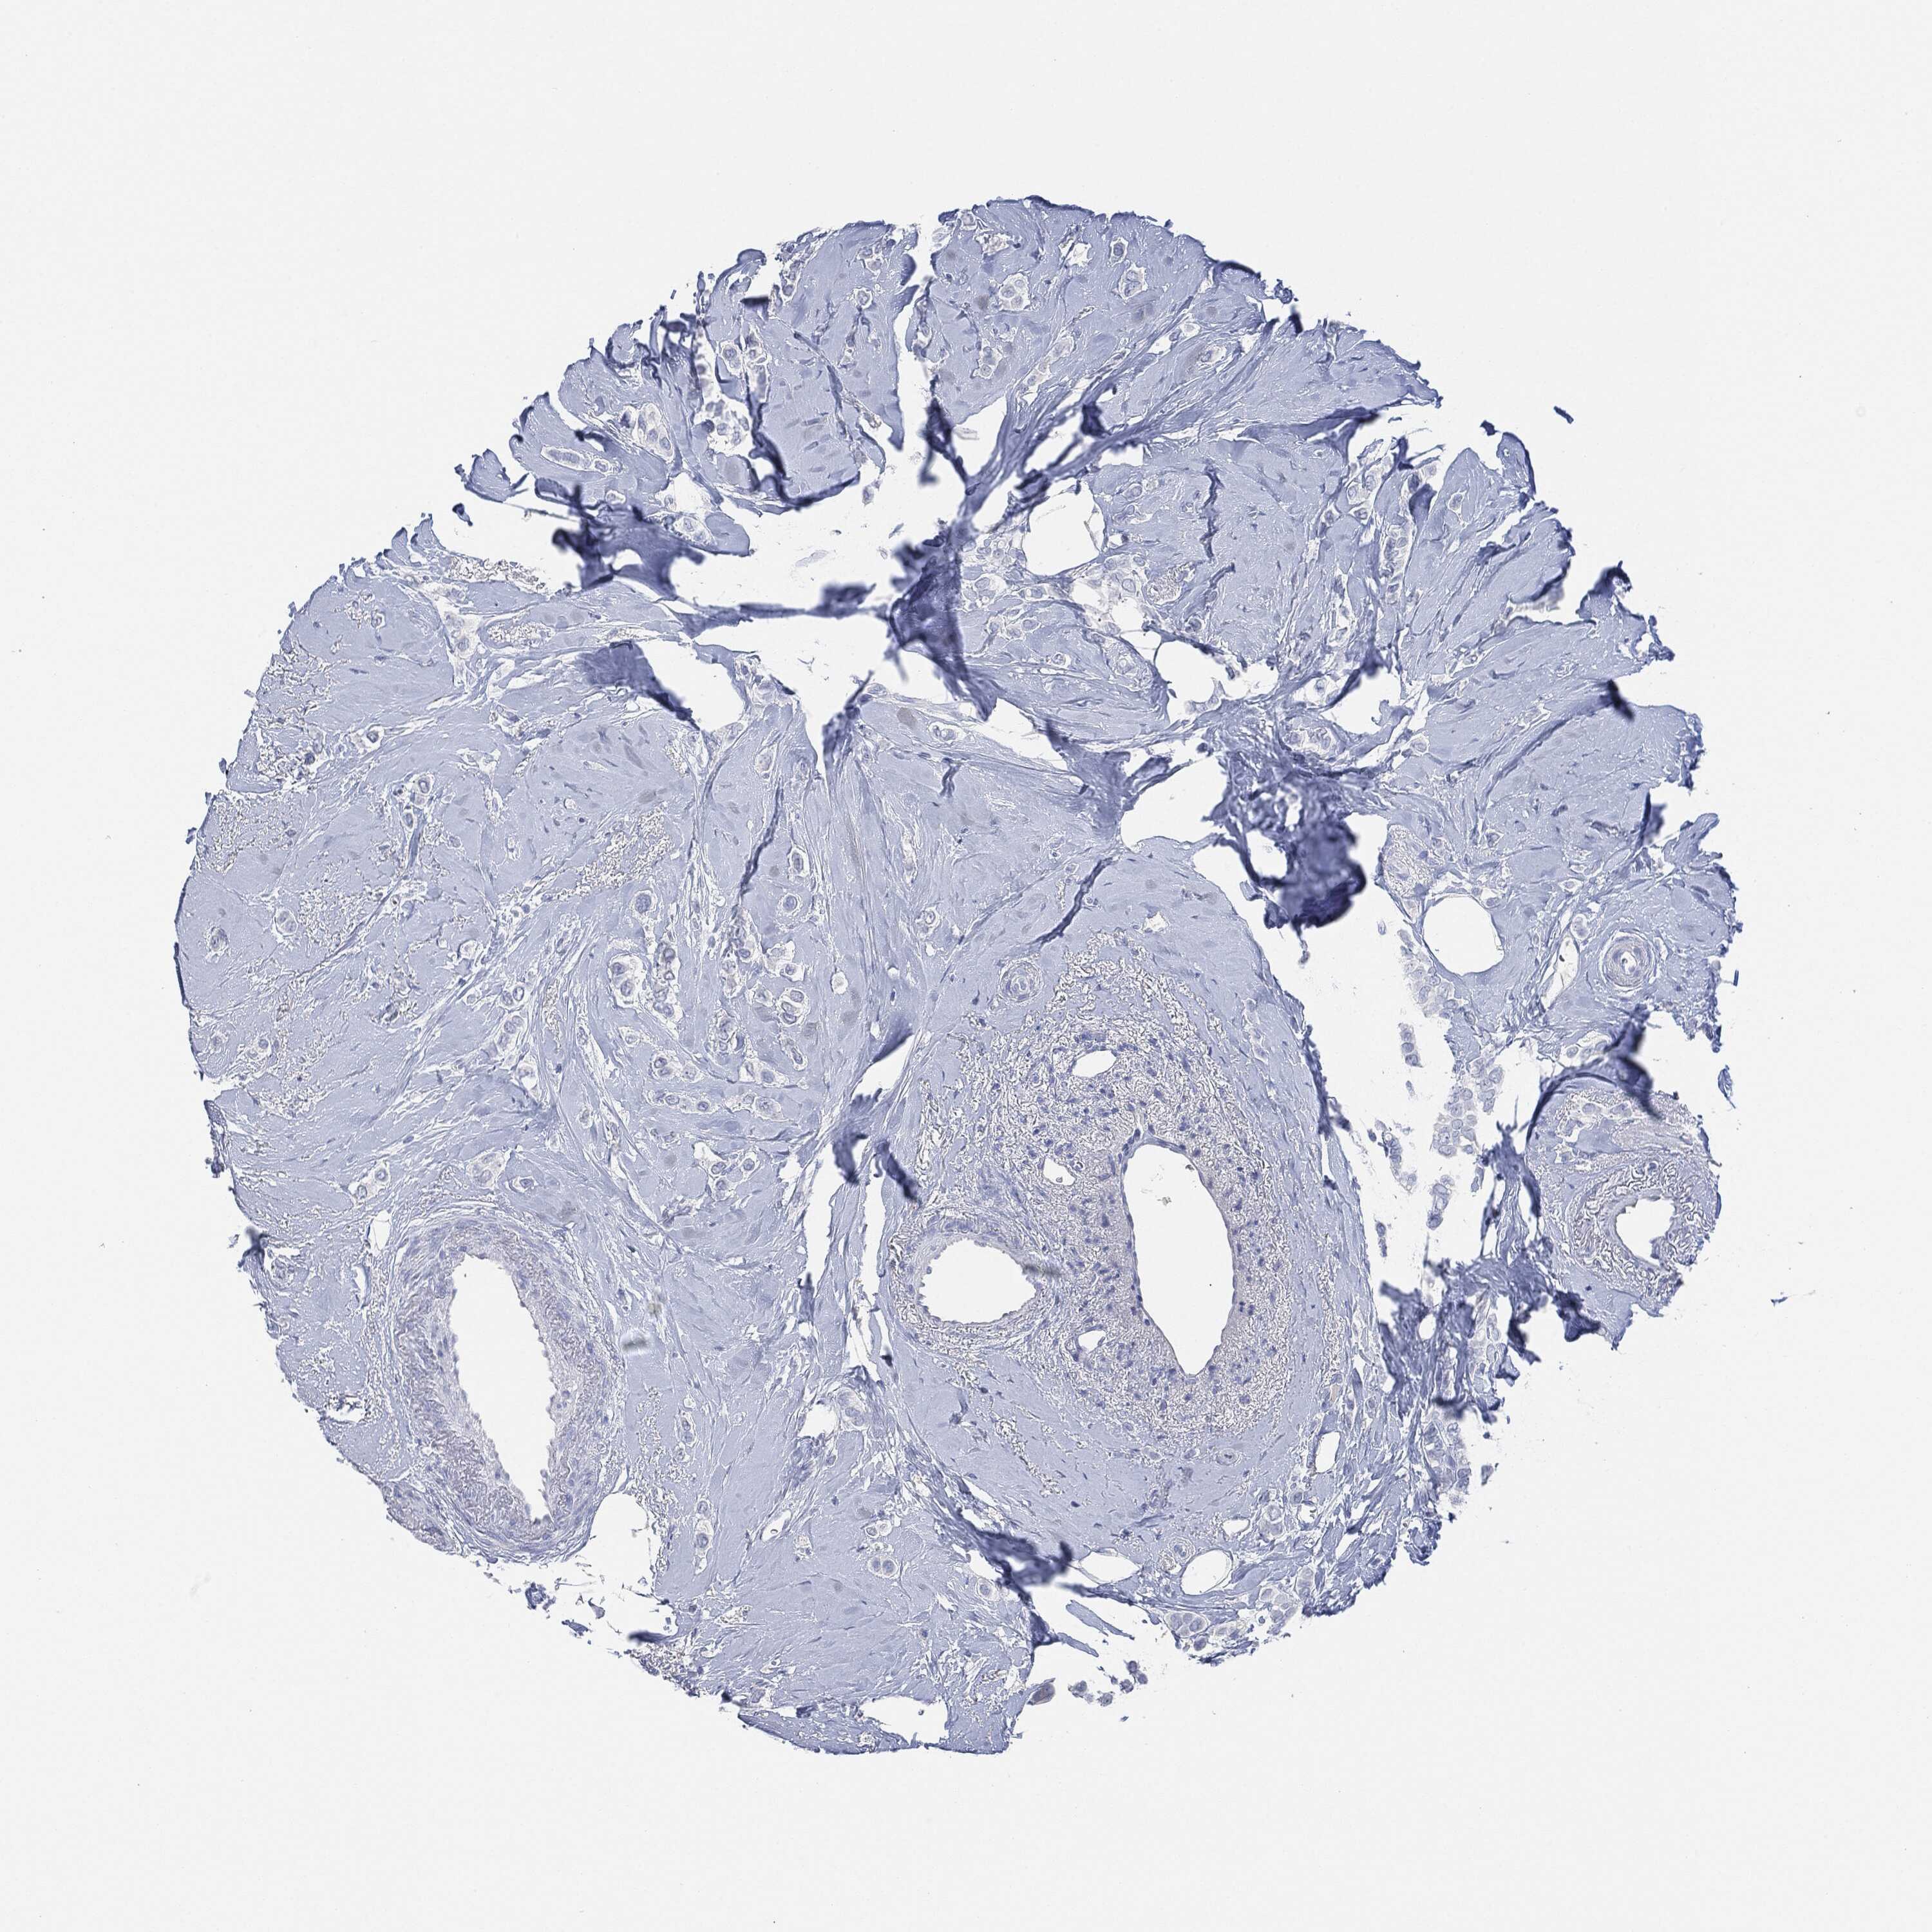

CANCER BREAST CANCER Show tissue menu

BRCA TCGA BRCA VALIDATION PROTEIN EXPRESSION

Breast cancer

Human cancer